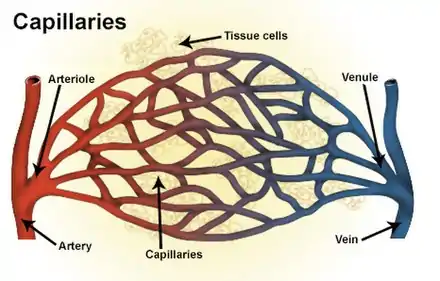

Types of blood vessels, including an arteriole and artery, as well as capillaries. | |

An arteriole is a small-diameter blood vessel in the microcirculation that extends and branches out from an artery and leads to capillaries.[1]

Arterioles have muscular walls (usually only one to two layers of smooth muscle cells) and are the primary site of vascular resistance. The greatest change in blood pressure and velocity of blood flow occurs at the transition of arterioles to capillaries. This function is extremely important because it prevents the thin, one-layer capillaries from exploding upon pressure. The arterioles achieve this decrease in pressure, as they are the site with the highest resistance (a large contributor to total peripheral resistance) which translates to a large decrease in the pressure.[2]

The decreased velocity of flow in the capillaries increases the blood pressure, due to Bernoulli's principle. This induces gas and nutrients to move from the blood to the cells, due to the lower osmotic pressure outside the capillary. The opposite process occurs when the blood leaves the capillaries and enters the venules, where the blood pressure drops due to an increase in flow rate. Arterioles receive autonomic nervous system innervation and respond to various circulating hormones in order to regulate their diameter. Retinal vessels lack a functional sympathetic innervation.[3]